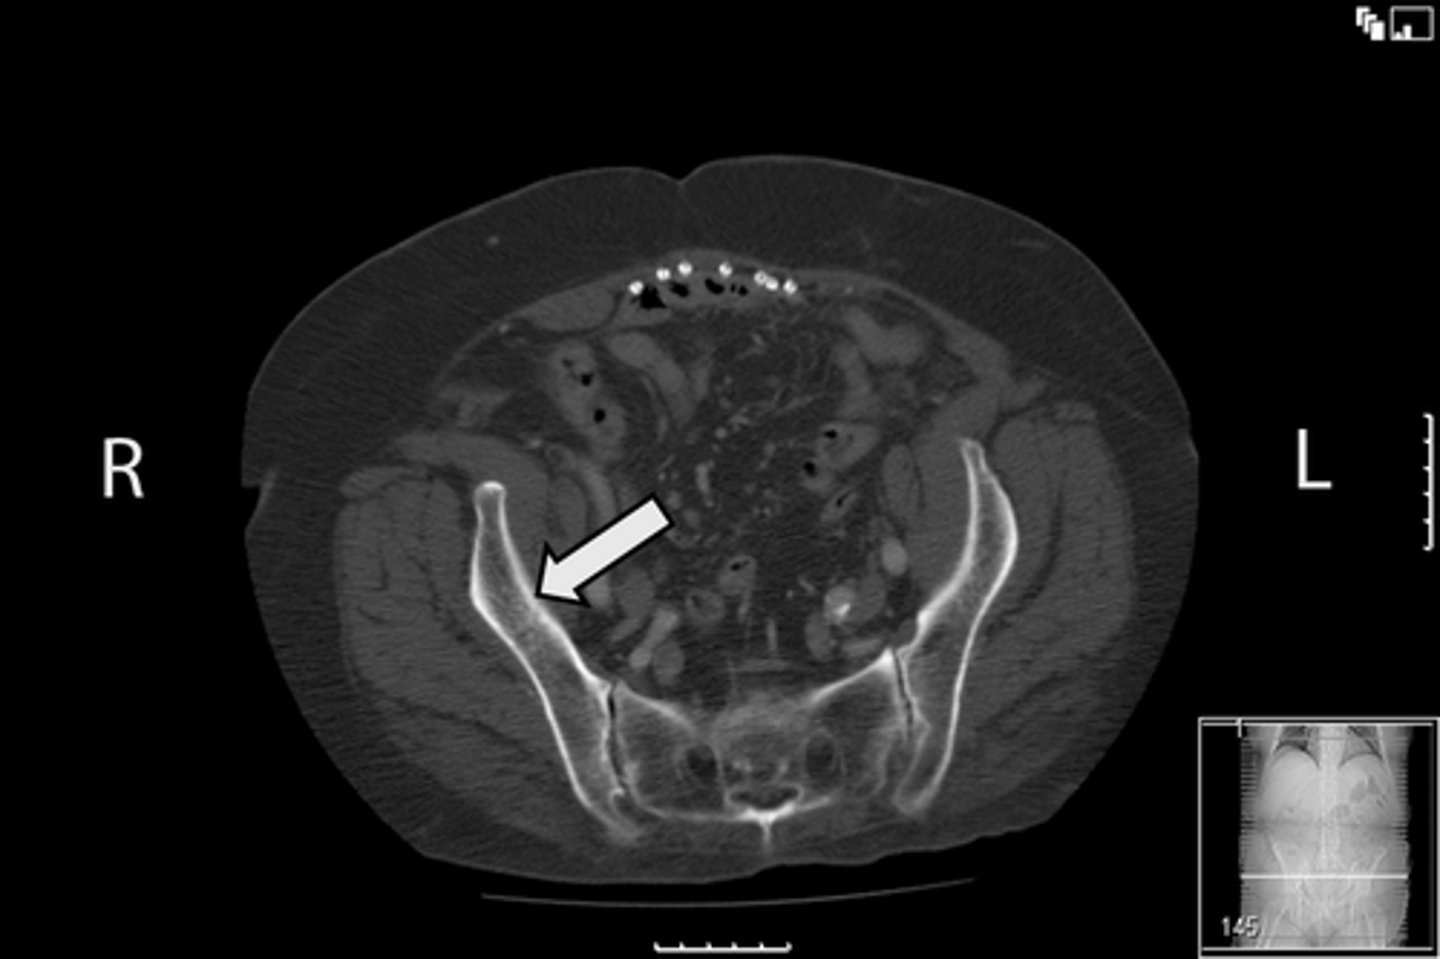

Axial bony pelvis CT

What is the image?

<p>What is the image?</p>

32

New cards

L ilium

What is indicated in the image?

<p>What is indicated in the image?</p>

33

L sacroiliac joint

34

R ilium

35

R sacroiliac joint

36

Sacrum